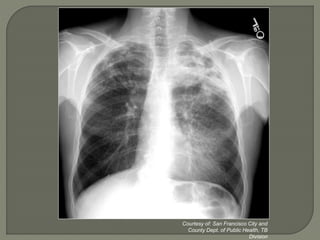

Obtain chest x-ray for patients with positive

TST results or with symptoms suggestive

Chest X-Ray (CXR) can support a

diagnosis of PTB

• Not used routinely for follow-up

• PTB can exist with normal CXR

• Must be interpreted with other information

 History and exam

 Sputum smear results

Courtesy of: San Francisco City and

County Dept. of Public Health, TB

Division